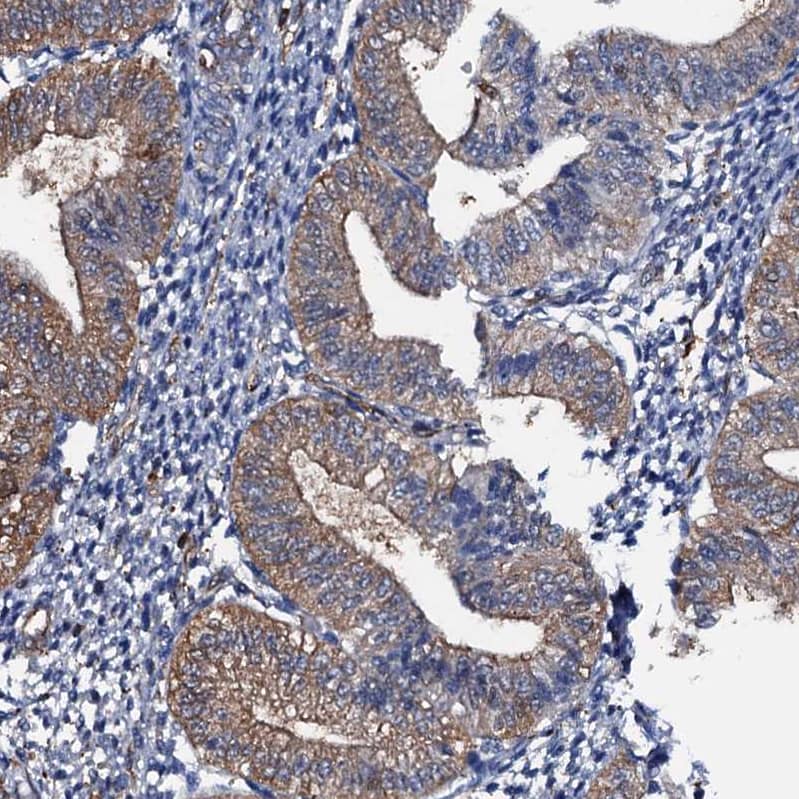

Staining of human small intestine shows strong membranous-cytoplasmic positivity in glandular cells.